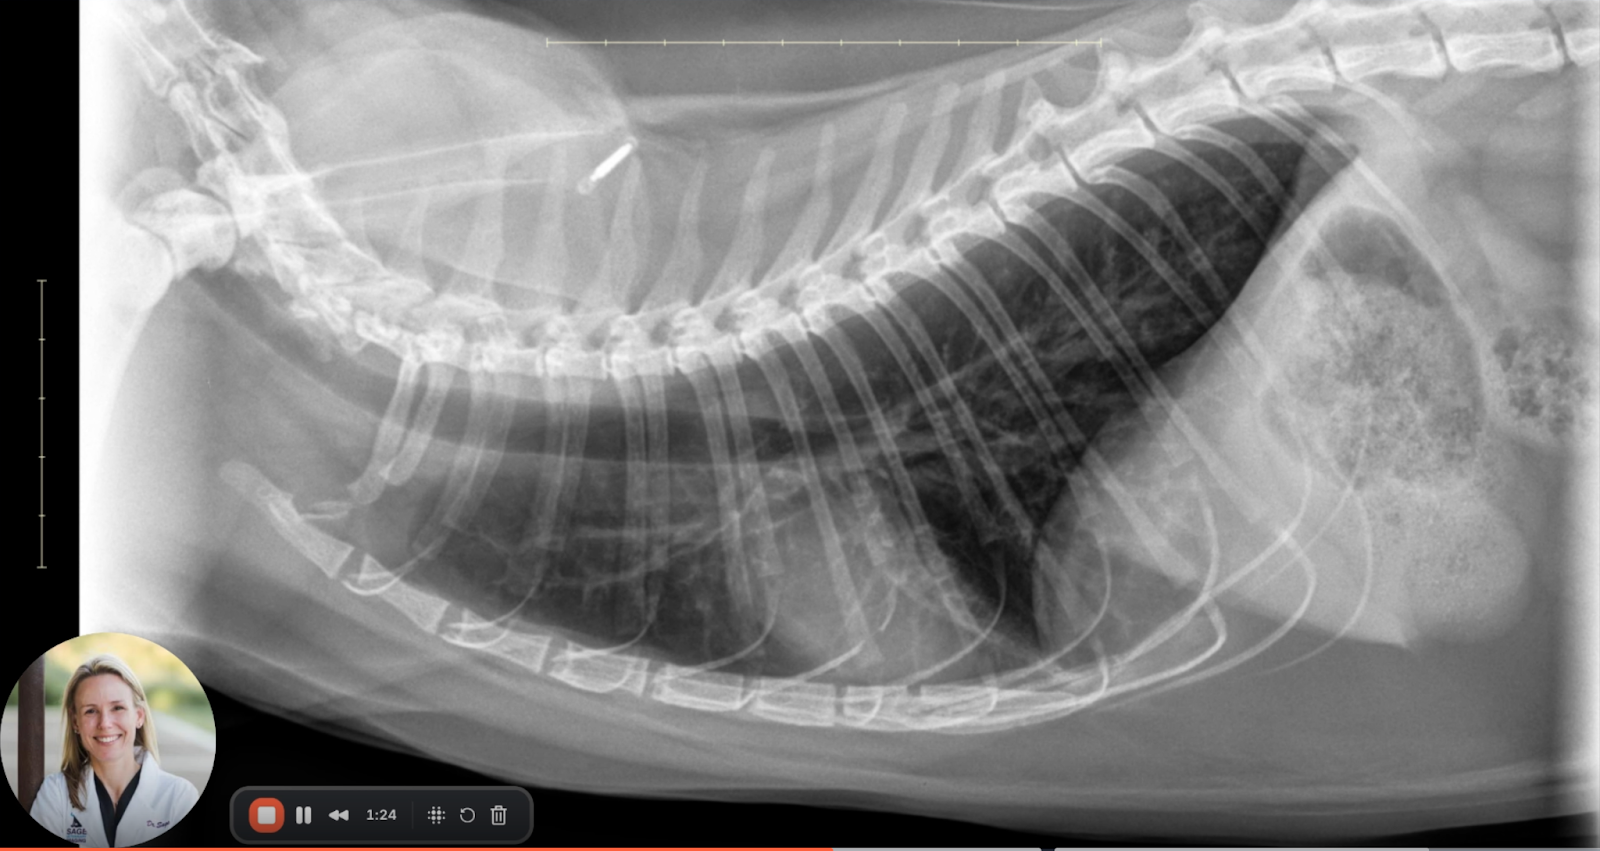

Image 4: Overview

Across all views, the radiographic features are consistent with:

• Diffuse bronchial wall thickening (donut and railroad signs)

• Pulmonary hyperinflation (flattened diaphragm, increased thoracic volume)

• Dilated intrathoracic trachea (indicative of expiratory airflow limitation)

These findings support a diagnosis of chronic lower airway disease (CLAD), with feline asthma being the most probable etiology given the patient's age, clinical signs, and radiographic appearance.